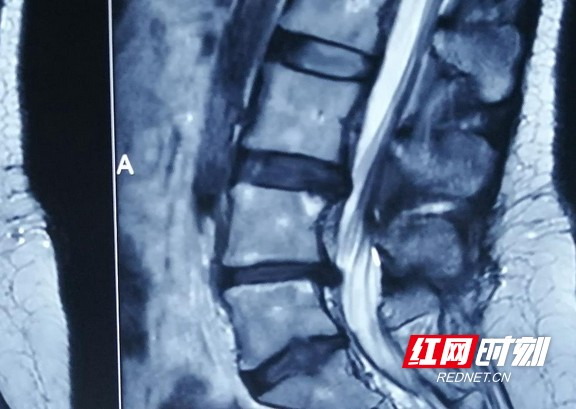

患者检查影像。

近期,宋女士腰部和腿部出现麻木和疼痛,行走距离稍长便需坐下休息。尽管休息和用药均未能有效缓解症状,她还是决定前往长沙骨质增生医院寻求治疗。通过MRI、CT等检查,医生确诊为腰椎间盘突出,突出的组织压迫了神经,并引发了无菌性炎症,这些因素共同导致了她的腰腿疼痛和跛行。尽管宋女士的病情并不复杂,但若不及时治疗,神经可能会受到损伤,恢复困难,甚至可能引发瘫痪等严重后果。确诊病情后,医院为她实施了微创椎间孔镜手术,借助一个仅黄豆般大小的0.6厘米切口,成功摘除了突出的髓核组织。术后,她的症状显著减轻,第二天便能够自由活动。经过数日的观察和治疗问鼎娱乐下载链接入口,宋女士已经完全康复,顺利出院。